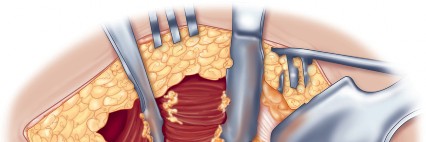

Optimizing Exposure with the Sharp Curved Hohmann

Once the anterior capsular exposure is achieved, a T-shaped or H-shaped capsulotomy is performed. The hip is then dislocated anteriorly with external rotation, extension, and adduction. After the femoral neck osteotomy is completed and the femoral head is removed, attention turns to acetabular preparation.

Acetabular exposure is the most technically demanding aspect of the lateral approach. To optimize exposure, the strategic placement of retractors is paramount. A sharp curved Hohmann retractor is carefully placed over the anterior lip of the acetabulum. The sharp tip must engage the bone securely to prevent slippage. This retractor serves a dual purpose: it retracts the anterior capsule and the elevated abductor-vastus flap anteriorly, providing unimpeded visualization of the anterior and superior acetabular rim.

Additional retractors are utilized to complete the exposure. A blunt Hohmann or Cobra retractor is placed inferiorly beneath the transverse acetabular ligament to retract the inferior capsule and soft tissues. A third retractor may be placed posteriorly. The precise placement of the anterior sharp curved Hohmann is the key to preventing the abductor mass from obscuring the surgeon's view during reaming and cup impaction.